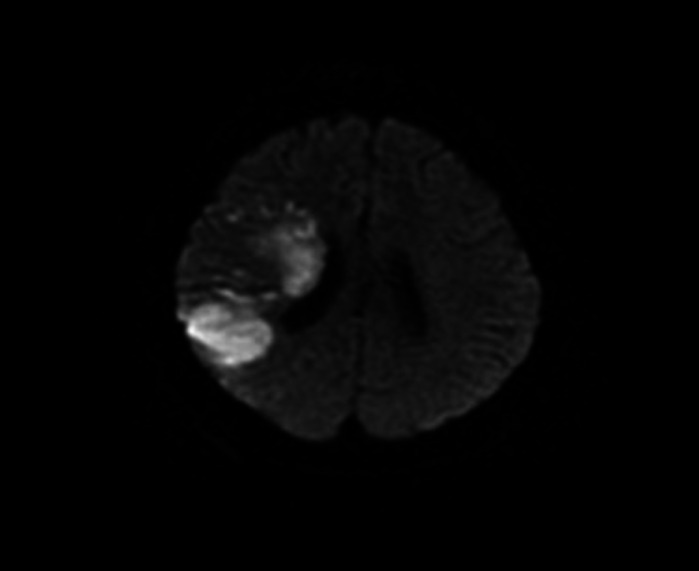

栓塞物质在身体的许多部位形成,可影响身体的任何部位。肺栓塞和栓塞性中风是体内栓塞性疾病最常见的表现形式。栓塞事件有不同的起因,而心脏是栓塞最重要的起源部位之一。非细菌性血栓性心内膜炎(NBTE)是导致栓塞事件的不常见原因之一,可发生在晚期癌症患者身上。NBTE 可导致栓塞。栓塞可能发生在一些器官,包括中枢神经系统、肾脏、脾脏、四肢和冠状动脉。作者旨在描述一例乳腺癌女性患者因非细菌性血栓性心内膜炎(NBTE)并发肺栓塞(PE)和栓塞性中风的罕见病例。

Embolic material forms in many parts of the body and can affect anywhere in the body. Pulmonary embolism and embolic stroke are the most common presentations of embolic disorders in the body. Embolic events have different causes, and the heart is one of the most important places where emboli originate. One of the uncommon causes of embolic events is non-bacterial thrombotic endocarditis (NBTE), which can occur in patients with advanced cancer. NBTE can lead to embolism. Embolisation may occur in some organs including the central nervous system, kidneys, spleen, limb extremities, and coronary arteries. The authors aim to describe a rare case with concurrent pulmonary embolism (PE) and embolic stroke caused by non-bacterial thrombotic endocarditis (NBTE) in a woman with breast cancer.